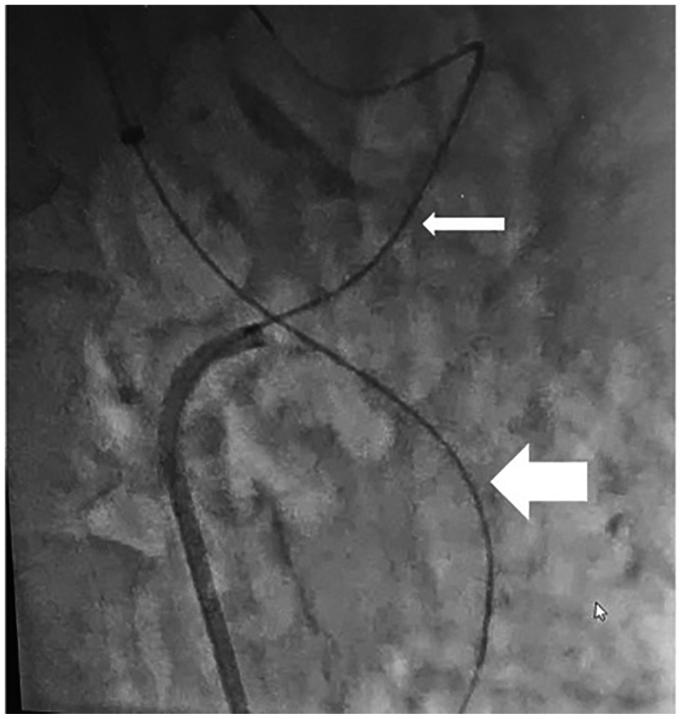

The celiacomesenteric trunk (CMT) is a rare anatomical variant where the celiac axis and superior mesenteric artery share a common origin. Despite its rarity, CMT has significant implications across various medical fields, particularly in surgical planning and interventional procedures. We report a case of chronic mesenteric ischemia owing to atherosclerotic stenosis at the CMT bifurcation, necessitating a complex interventional approach. Kissing covered stent angioplasty was successfully performed, resulting in revascularization, symptom resolution, and no restenosis at 1-year follow-up. This report highlights the feasibility and effectiveness of the kissing stent technique in managing complex CMT bifurcation obstructions in patients with chronic mesenteric ischemia.

腹腔肠系膜干(CMT)是一种罕见的解剖变异,即腹腔干和肠系膜上动脉有共同的起源。尽管CMT罕见,但它在各个医学领域都有重要意义,尤其是在手术规划和介入操作方面。我们报告一例因CMT分叉处动脉粥样硬化狭窄导致的慢性肠系膜缺血病例,需要采用复杂的介入方法。成功实施了吻合法覆膜支架血管成形术,实现了血管再通、症状缓解,且在1年随访时无再狭窄。本报告强调了吻合法支架技术在处理慢性肠系膜缺血患者复杂CMT分叉处梗阻方面的可行性和有效性。